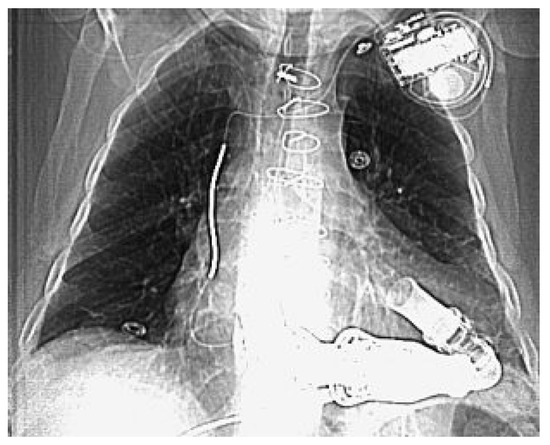

Links-Ventrikuläre Assist Devices—Indikationen und Möglichkeiten

by Ludwig K. von Segesser, Piergiorgio Tozzi, Enrico Ferrai, Sandra Bommeli, Lars Niclauss, Dominique Delay, Philippe Gersbach, Michel Hurni, Bettina Marty, Patrick Ruchat and Frank Stumpe

Heart failure not responding to medical therapy is either due to left ventricular failure, right ventricular failure or bi-ventricular failure. Left ventricular assist devices are designed for left ventricular mechanical circulatory support and not suitable for treatment of advanced global cardiac failure which [...] Read more.

Heart failure not responding to medical therapy is either due to left ventricular failure, right ventricular failure or bi-ventricular failure. Left ventricular assist devices are designed for left ventricular mechanical circulatory support and not suitable for treatment of advanced global cardiac failure which deteriorates rapidly towards irreversible multi organ failure. Although temporary right ventricular support may be necessary during left mechanical circulatory support, it should be the goal that this is the exception and not the rule. This statement is based on the experience, that predominantly left ventricular failure can be handled well with the timely application of modern implantable left ventricular assist devices which allow usually for relative rapid recovery towards a quite normal life.

We mean here not only weaning from the ventilator, extubation, mobilisation, and the transfer from the intensive care unit to the general hospital ward, but rather the discharge home with a quite good quality of life over a longer time frame despite the machine dependence which requires in our program a weekly outpatient check of the patient with his hard and software. Full article

Figure 1